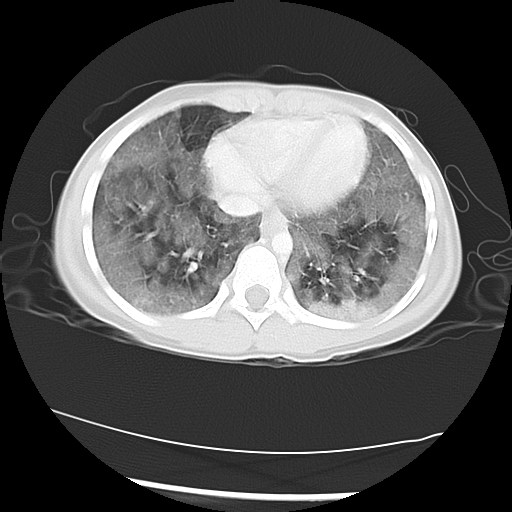

The following screen shows the images from the Chest CT:

| Figure 2-a | Figure 2-b | Figure 2-c |

| Figure 2-d | Figure 2-f |